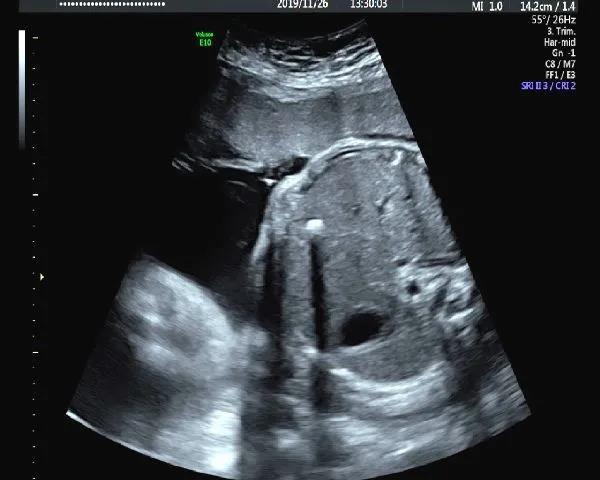

超声较为常见的描述“强回声、强光点”是怎么回事?都说少年强则国强,孕期胎儿“强”,到底是不是好事儿呢?

下面和宝妈们分享孕期常见的那些“强回声、强光点”。

1.心脏强回声

心室强光点是孕期最为常见的强回声,这些孤立的强回声不会影响心功能,也不是胎儿心脏的结构异常的表现,一般孕晚期会消失,有时会追溯到新生儿期。其在正常胎儿中发生率在2%-5%。

宝妈们遇到这样的报告,如果染色体异常筛查低风险,我们可以选择乐观一些。但对本身存在染色体异常高风险的人群还是要更谨慎一些,要听听产科医生的意见。